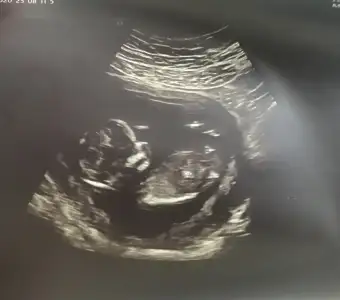

• 1000024109.webp

1000024109.webp

38,8 KB · Görüntüleme: 22